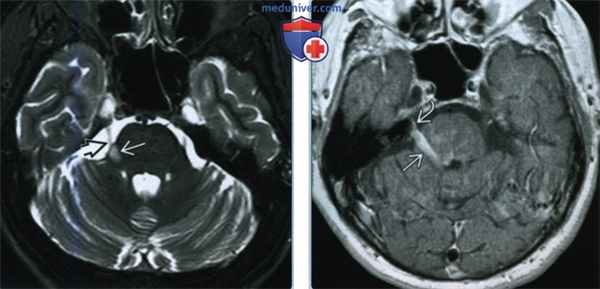

(Слева) При аксиальной МРТ Т2 ВИ FS у пациента с правосторонней ТН определяются множественные склеротические очаги в наружных отделах моста в области вхождения корешка тройничного нерва. PC или цистернальные объемные образования редко могут проявляться ТН.

(Справа) При аксиальной МРТ Т1 ВИ С+ у пациента с правосторонней ТН определяется врожденная аномалия вен мозжечка, дренирующихся через наружные отделы моста и область вхождения корешка ЧН V. ТН обусловлена патологией вен лишь у 5% пациентов.